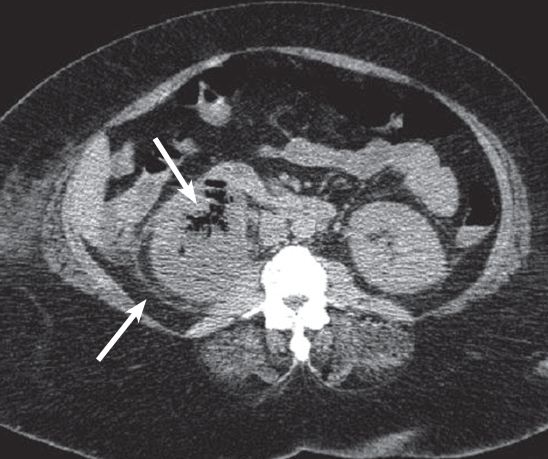

A 44-year old male with history of chronic hypertension presented with 1-month history of nausea, fatigue, and decreased appetite.